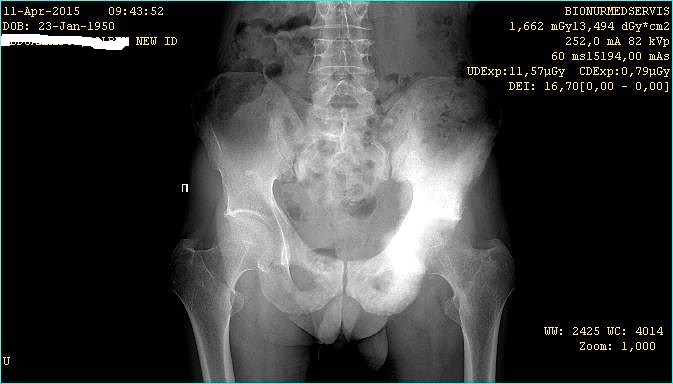

Христос Воскресе! Здравствуйте уважаемые коллеги. Хочу просить помощи в

анализе

представленного снимка. Пациент прислал по сети и попросили

прокомментировать. У меня возникли затруднения с дифференцировкой

данного новообразования и поэтому прошу помощи коллег, возможно, кто-то

встречал в своей практике подобные случаи.